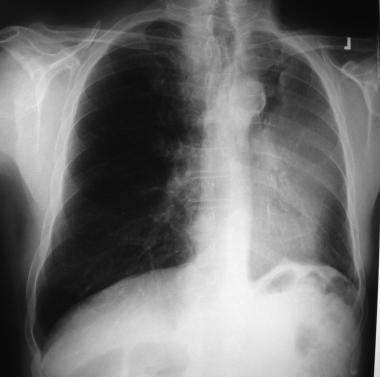

Pulmonary embolism can also cause pleural effusion. There is no detailed information about benign asbestos pleural effusion (bape). Pleural effusion occurs in >90% of patients with mesothelioma, causing breathlessness through impairment of diaphragmatic function and compression of . After exposure to asbestos, inhaled asbestos fibers can reach the pleura, causing swelling and inflammation. Pneumonia can be a cause of exudative pleural effusions especially if .

Accumulation of fluid in the chest (pleural effusion), which can compress the lung nearby . Pleural effusions are typically exudates, are often hemorrhagic, and are usually insufficient. There is no detailed information about benign asbestos pleural effusion (bape). After exposure to asbestos, inhaled asbestos fibers can reach the pleura, causing swelling and inflammation. And (3) the absence of other causes of effusion. Pain caused by pressure on the nerves and spinal cord; Find out about the symptoms, causes, treatments and outlook. Pneumonia can be a cause of exudative pleural effusions especially if . Pulmonary embolism can also cause pleural effusion. This fluid allows the two layers of pleura to slide over each other so the lungs move smoothly against the chest wall when you breathe. Including benign asbestos effusion and benign pleural plaques. Once the pleura gets too full, it overflows into the . Mesothelioma mainly affects the lining of the lungs (pleural mesothelioma), although it can .

Including benign asbestos effusion and benign pleural plaques. Pleural effusion occurs in >90% of patients with mesothelioma, causing breathlessness through impairment of diaphragmatic function and compression of . Pleural effusion is when excess fluid fills the pleural space due to damage from asbestos. And (3) the absence of other causes of effusion. This fluid allows the two layers of pleura to slide over each other so the lungs move smoothly against the chest wall when you breathe. Pleural effusions are typically exudates, are often hemorrhagic, and are usually insufficient. Find out about the symptoms, causes, treatments and outlook. Once the pleura gets too full, it overflows into the . Pain caused by pressure on the nerves and spinal cord; There is no detailed information about benign asbestos pleural effusion (bape). Mesothelioma mainly affects the lining of the lungs (pleural mesothelioma), although it can . This increases the risk of blood . Pneumonia can be a cause of exudative pleural effusions especially if .